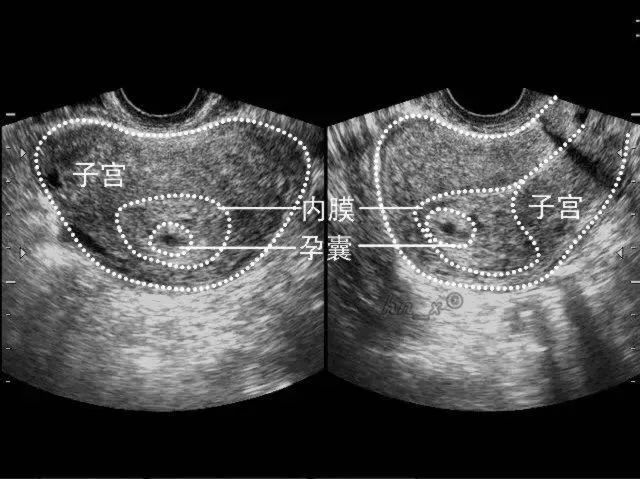

宫内真假孕囊的鉴别

真孕囊与假孕囊的区别

可以用于和异位妊娠的单蜕膜征(单囊征)或假孕囊(pseudo-sac)的鉴别.

囊是宫内妊娠的重要标志,它的出现可以排除宫外妊娠时宫内的假孕囊